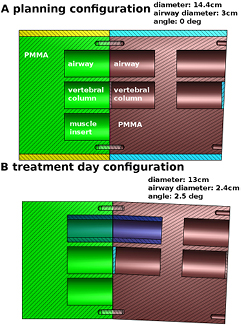

A phantom specific to H & N deformations was built for this study. The phantom was designed to simulate the main deformations observed in H & N patients: weight loss, neck tilt in the anterior–posterior direction and variation of airway diameter due either to tumor volume changes or differences in the patient's position between planning CT and CBCT. The phantom, mainly consisting of PMMA, is presented in figure 1 and its components are described in table 1. The two non-PMMA materials, muscle and vertebral column were from CIRS (CIRS Inc, Norfolk, VA). We observed that in patient CT scans, the vertebral column had a CT number distribution centered at 650 HU and the vertebral column material was chosen to approximate this. The phantom was scanned at a planning CT (Toshiba Aquilion 16 LB, Toshiba Medical Systems, the Netherlands) using the clinical protocol for H & N patients in the planning configuration (no neck tilt, 14.4 cm diameter, airway diameter of 3 cm, figure 1(a)) and in treatment day configuration (2.5 degree neck tilt, 13 cm diameter and airway diameter of 2.4 cm, figure 1(b)). Images were reconstructed with 3 mm slice thickness and 1.074 mm voxel size in the axial plane. While registration results could potentially be improved by reconstructing images with thinner slices (1 or 2 mm), we used 3 mm to be consistent with patient data on which the method is to be applied.

Figure 1. (a) Planning configuration: PMMA deformable phantom modeling H & N anatomical changes. All cavities are 3 cm in diameter and accommodate 5 cm long inserts. The phantom diameter as shown is 14.4 cm. The central channels contain vertebral column mimicking inserts, the top channels are kept empty to represent airways and the lower channel contains a muscle mimicking insert for soft tissue contrast. (b) Treatment day configuration: weight loss is modeled by the removal of the yellow and light blue sleeves, reducing the diameter to 13 cm. 2.5° neck tilt is modeled by reversing the red right half of the phantom. Airway diameter variation is modeled by inserting a thin sleeve (dark blue) in both airway channels, reducing the diameter from 3 to 2.4 cm. Two PMMA spacers, one for each angle configuration, are used between the two vertebral column inserts.

The treatment day CT scan (refCT) served as ground truth for deformation evaluation. The phantom modification causing the largest volume change from the planning to the treatment day configuration was the removal of the outer ring to reduce the phantom diameter. To assess whether our validation was sensitive to the two other anatomy changes investigated, we included two additional configurations: airway diameter modification only and phantom angle modification only. Table 2 summarizes all the configurations. While tests were performed for each configuration, in this paper we focus on configuration 3 as it represents the combination of all effects.